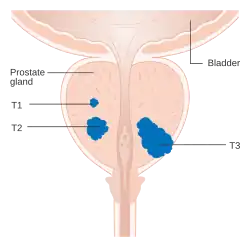

After diagnosis, the tumor is staged to determine the extent of its growth and spread. Prostate cancer is typically staged using the American Joint Committee on Cancer's (AJCC) three-component TNM system, with scores assigned for the extent of the tumor (T), spread to any lymph nodes (N), and the presence of metastases (M).[31] Scores of T1 and T2 represent tumors that remain within the prostate: T1 is for tumors not detectable by imaging or digital rectal exam; T2 is for tumors detectable by imaging or rectal exam, but still confined within the prostate.[32] T3 is for tumors that grow beyond the prostate – T3a for tumors with any extension outside the prostate; T3b for tumors that invade the adjacent seminal vesicles. T4 is for tumors that have grown into organs beyond the seminal vesicles.[32] The N and M scores are binary (yes or no). N1 represents any spread to the nearby lymph nodes. M1 represents any metastases to other body sites.[32]

The AJCC then combines the TNM scores, Gleason grade group, and results of the PSA blood test to categorize cancer cases into one of four stages, and their subdivisions. Cancer cases with localized tumors (T1 or T2), no spread (N0 and M0), Gleason grade group 1, and PSA less than 10 ng/mL are designated stage I. Those with localized tumors and PSA between 10 and 20 ng/mL are designated stage II – subdivided into IIA for Gleason grade group 1, IIB for grade group 2, and IIC for grade group 3 or 4. Stage III is the designation for any of three higher risk factors: IIIA is for a PSA level about 20 ng/mL; IIIB is for T3 or T4 tumors; IIIC is for a Gleason grade group of 5. Stage IV is for cancers that have spread to lymph nodes (N1, stage IVA) or other organs (M1, stage IVB).[31]